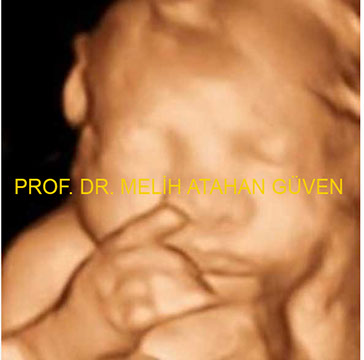

4 BOYUTLU RESİMLER